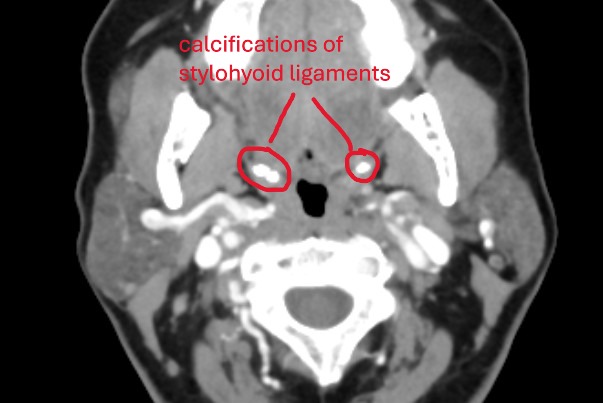

@chrEagle see attached annoted images (5 here of the axial view, and a 3D model in a following post)

Further down, there is a pocket of calcified stylohyoid ligament on both sides. It may not look like much, but these little calcification pockets can irritated nerves.